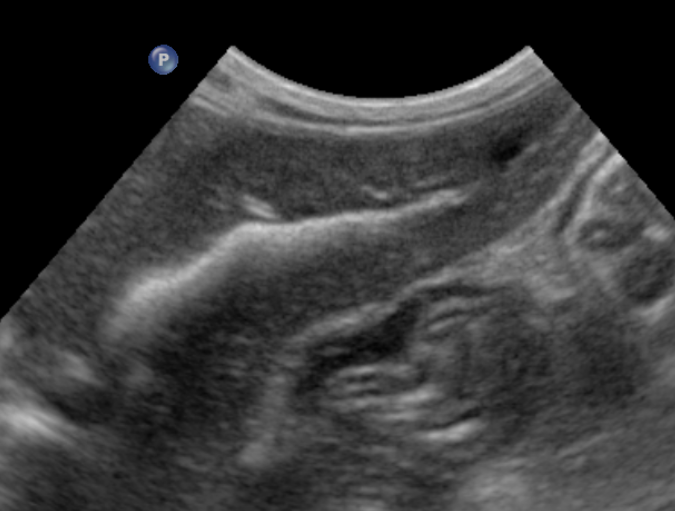

feline intrahepatic bile calculi : radiography

ultrasonography

branched intrahepatic bile duct stone